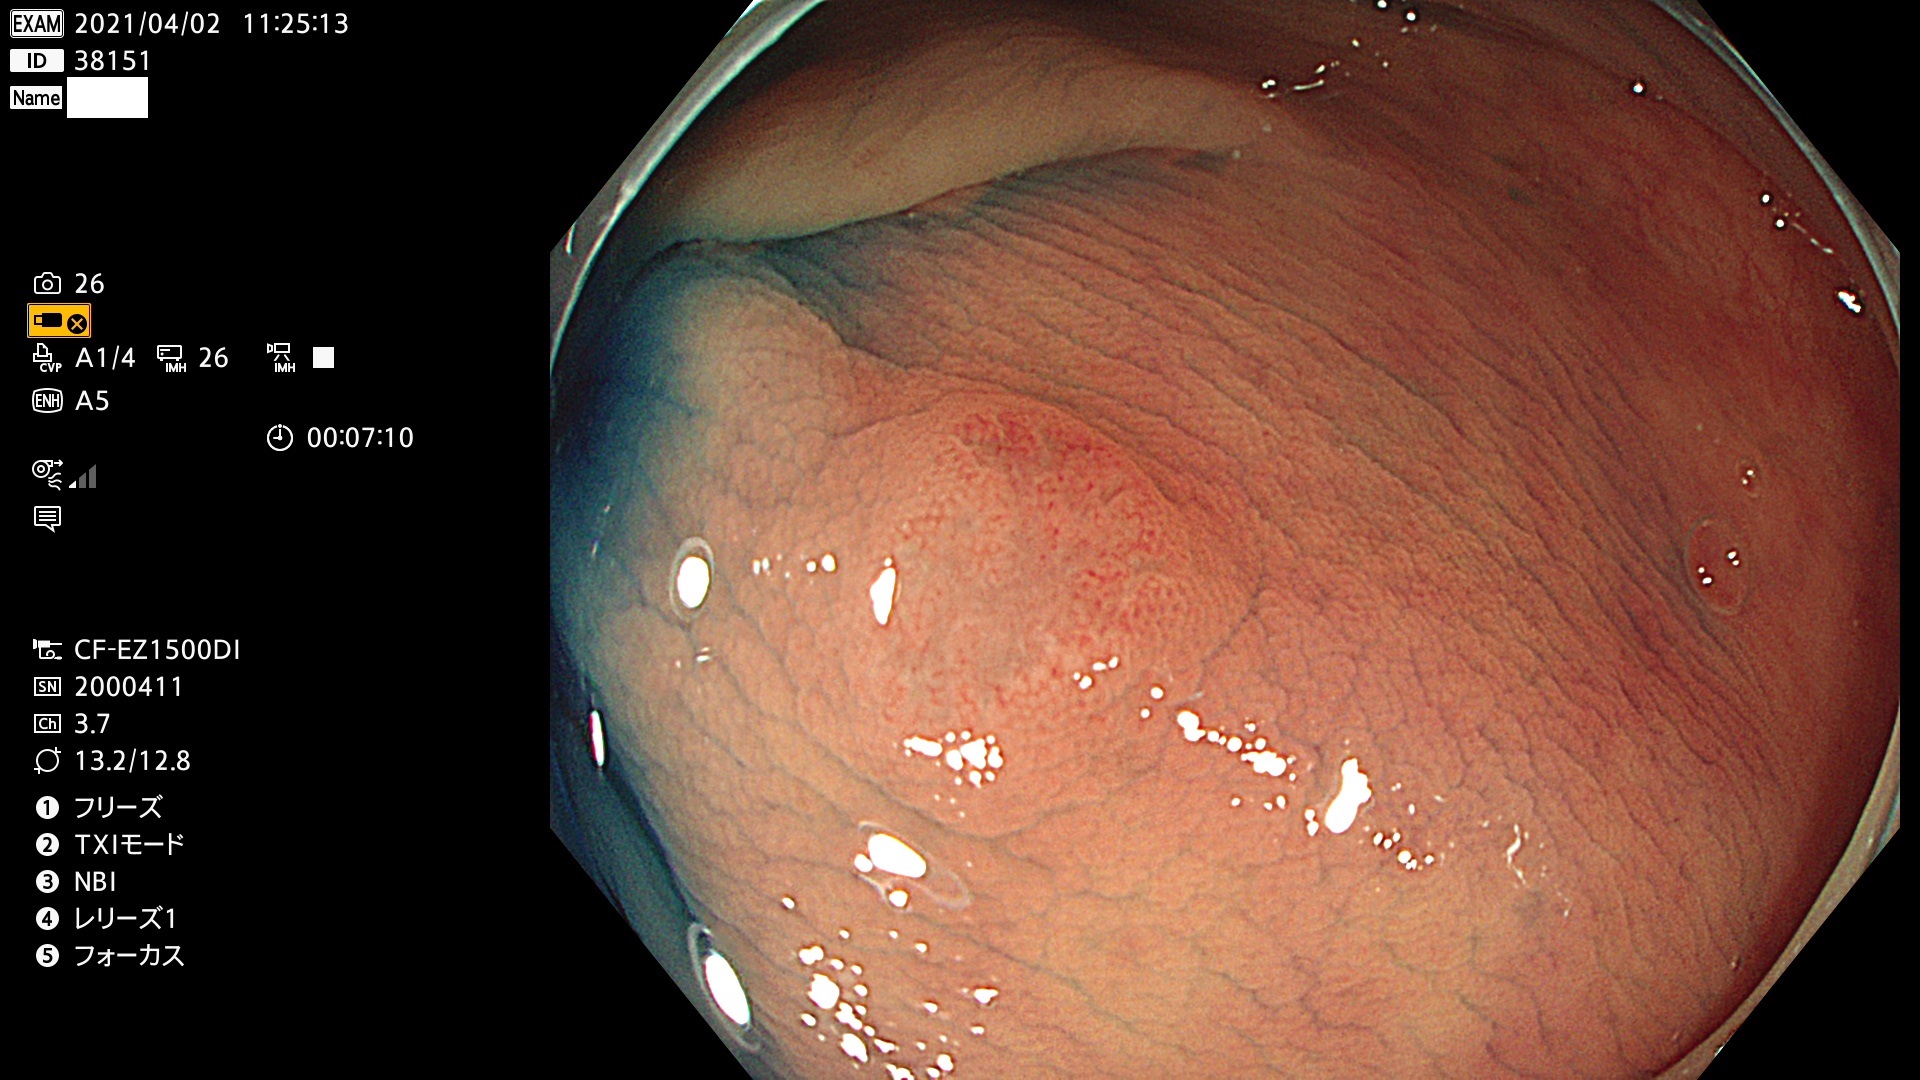

腺腫発見率 72 % (カルテ番号 38100〜38199の100名の方の検査結果で集計)大腸癌検診最新情報

以下のカルテ番号の方に腺腫(Adenoma,Group3〜5)が見つかりました(集計法)

38101 38103 38104 38106 38107 38108 38109 38110 38111 38112 38113 38114 38115 38117 38118 38122 38123 38124 38125 38126 38127 38128 38130 38131 38132 38135 38137 38138 38140 38141 38142(SSAPのみ) 38143 38144 38145 38146 38147 38148 38149 38150 38151 38152 38153 38154 38157 38158 38160 38161 38162 38164 38165 38166 38167 38168 38169 38172 38176 38177 38178 38181 38182 38183 38184 38187 38189 38190 38191 38192 38193 38194 38195 38196(SSAPのみ) 38198

発見困難で危険性の高い平坦型病変(上記100名より抽出) ![]()